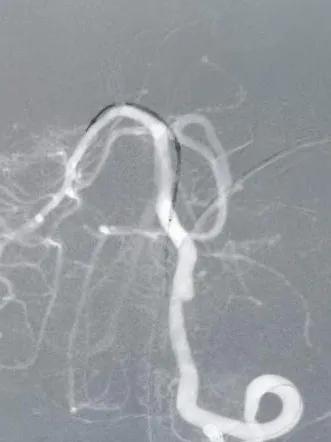

静脉肝素化,T-track支架导管微导丝导引下超选跨病变部位置入右侧大脑后动脉段。予以4.0×25mm Tubridge®血管重建装置于左椎动脉脊髓前动脉开口处近侧锚定缓慢释放,支架打开良好,贴壁完全。

支架置入过程